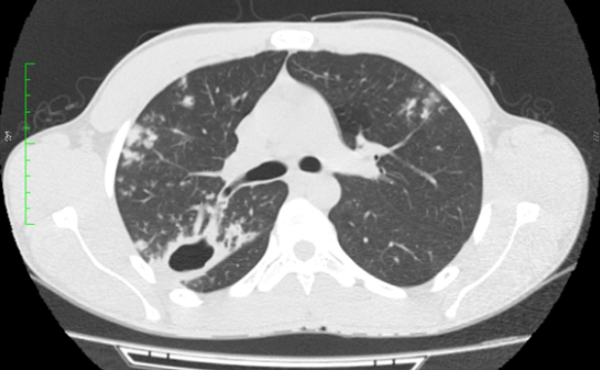

Paciente sexo masculino, 18 anos, sem comorbidades, com quadro arrastado de febre e perda ponderal há cerca de três meses. Foi realizado radiografia de tórax (não disponibilizada), com laudo inconclusivo. Optou-se por prosseguir investigação com tomografia computadorizada do tórax.

Diante das imagens, qual a melhor descrição e a principal hipótese diagnóstica?

CEscavação de paredes espessadas no lobo superior direito e nódulos com distribuição centrolobular dispersos pelo parênquima – tuberculose

DEscavação de paredes espessadas no lobo superior direito e nódulos com distribuição centrolobular dispersos pelo parênquima – aspergilose broncopulmonar alérgica